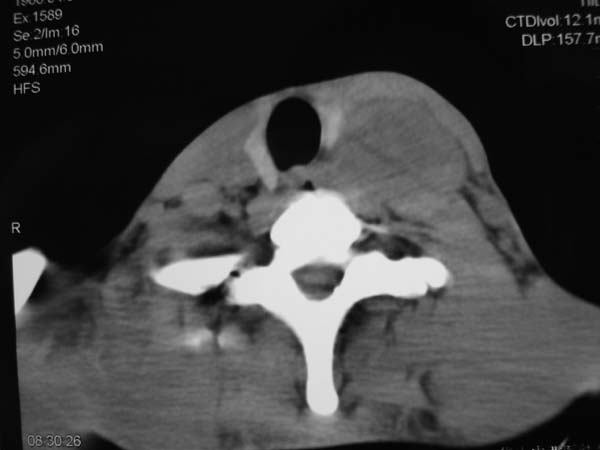

患者男性,37岁,农民,自觉左颈部肿大三天,无其它不适。

左侧颈部软组织密度肿块,界限清楚,形态不规则,占位效应明显。考虑:1 淋巴瘤。2 神经源性肿瘤不除外。

左颈部占位,病灶沿间隙分布,密度混浊,结合病史肿大三天,考虑1,炎症病变,建议增强。2,颈部血管性病变。

考虑神经源性肿瘤.

患者没有任何症状,炎性和淋巴瘤可能不是,主要是来源,有没有来自甲状旁腺的可能?

同甲状腺间有脂肪间隙存在,考虑不是来源于甲状腺,肿大淋巴结?

左侧甲状腺在那? 病变来自甲状腺吧,甲状腺肿或腺瘤

病灶边界较清,密度不均,其内可见坏死灶,左侧甲状腺受压,考虑神经源性肿瘤可能性大,建议穿刺活检。